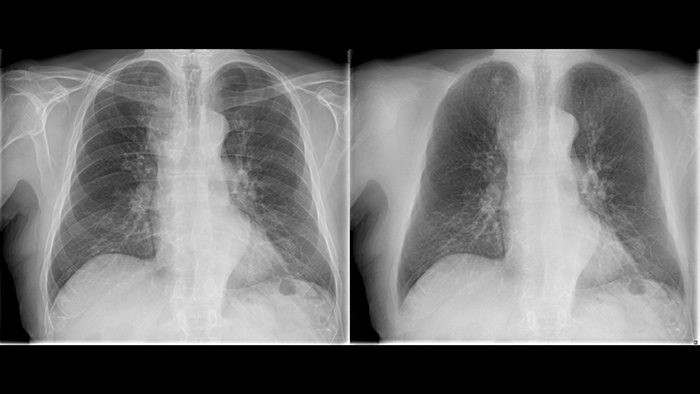

Improve your ability to provide confident diagnosis with two new image processing features

Philips UNIQUE 2 improves image quality with more homogeneous black backgrounds, reduced noise and automatic enhancement of small details

Philips Bone Suppression3 helps remove bone structures from chest images for an unobstructed view of soft tissue and can improve actionable nodule detection by up to 16.8% without the need to expose the patient to additional X-ray dose.4

Next generation image processing with Philips UNIQUE 2

Philips Bone Suppressionimproves actionable lung nodule detection up to 16.8%4